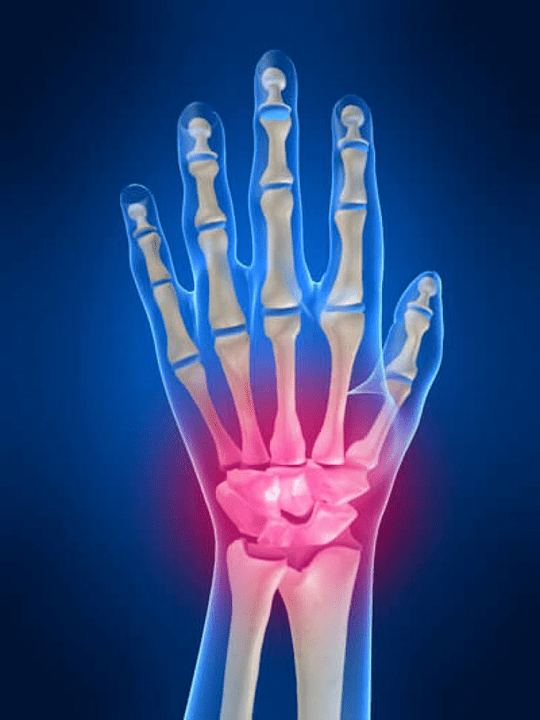

A articulación do pulso

A articulación do pulso está formada polos ósos dos ósos proximais (superior) unha serie de pulsos (ósos triédricos, semi -lúa, escafoides) e áreas distais de radiación e ósos do cóbado. O óso do cóbado non está directamente conectado aos ósos do pulso, senón coa axuda de distal (Baixa) o disco articular. Esta estrutura separa a cavidade da articulación do pulso da cavidade distal (Baixa) A articulación de tella.

Articulacións do pulso

As articulacións do pulso están representadas por tres tipos de articulacións. A primeira forma inclúe aquelas xuntas que se atopan entre os ósos da parte superior (escafoide, semi -lúa, triédrico, guisante) ou a fila inferior (en forma de gancho, de cabeza, trapezoidal, atrapamento óseo). Estas articulacións chámanse articulacións interchangena. Polo segundo tipo, clasifícase a articulación Mid -Wrist de chamada Mid -Wrist. Esta articulación ten unha forma en forma de S e fórmase debido á conexión dos ósos da fila superior e inferior do pulso. O terceiro tipo inclúe a articulación do óso de guisante. A través desta articulación, o óso triédrico está conectado ao óso do guisante.